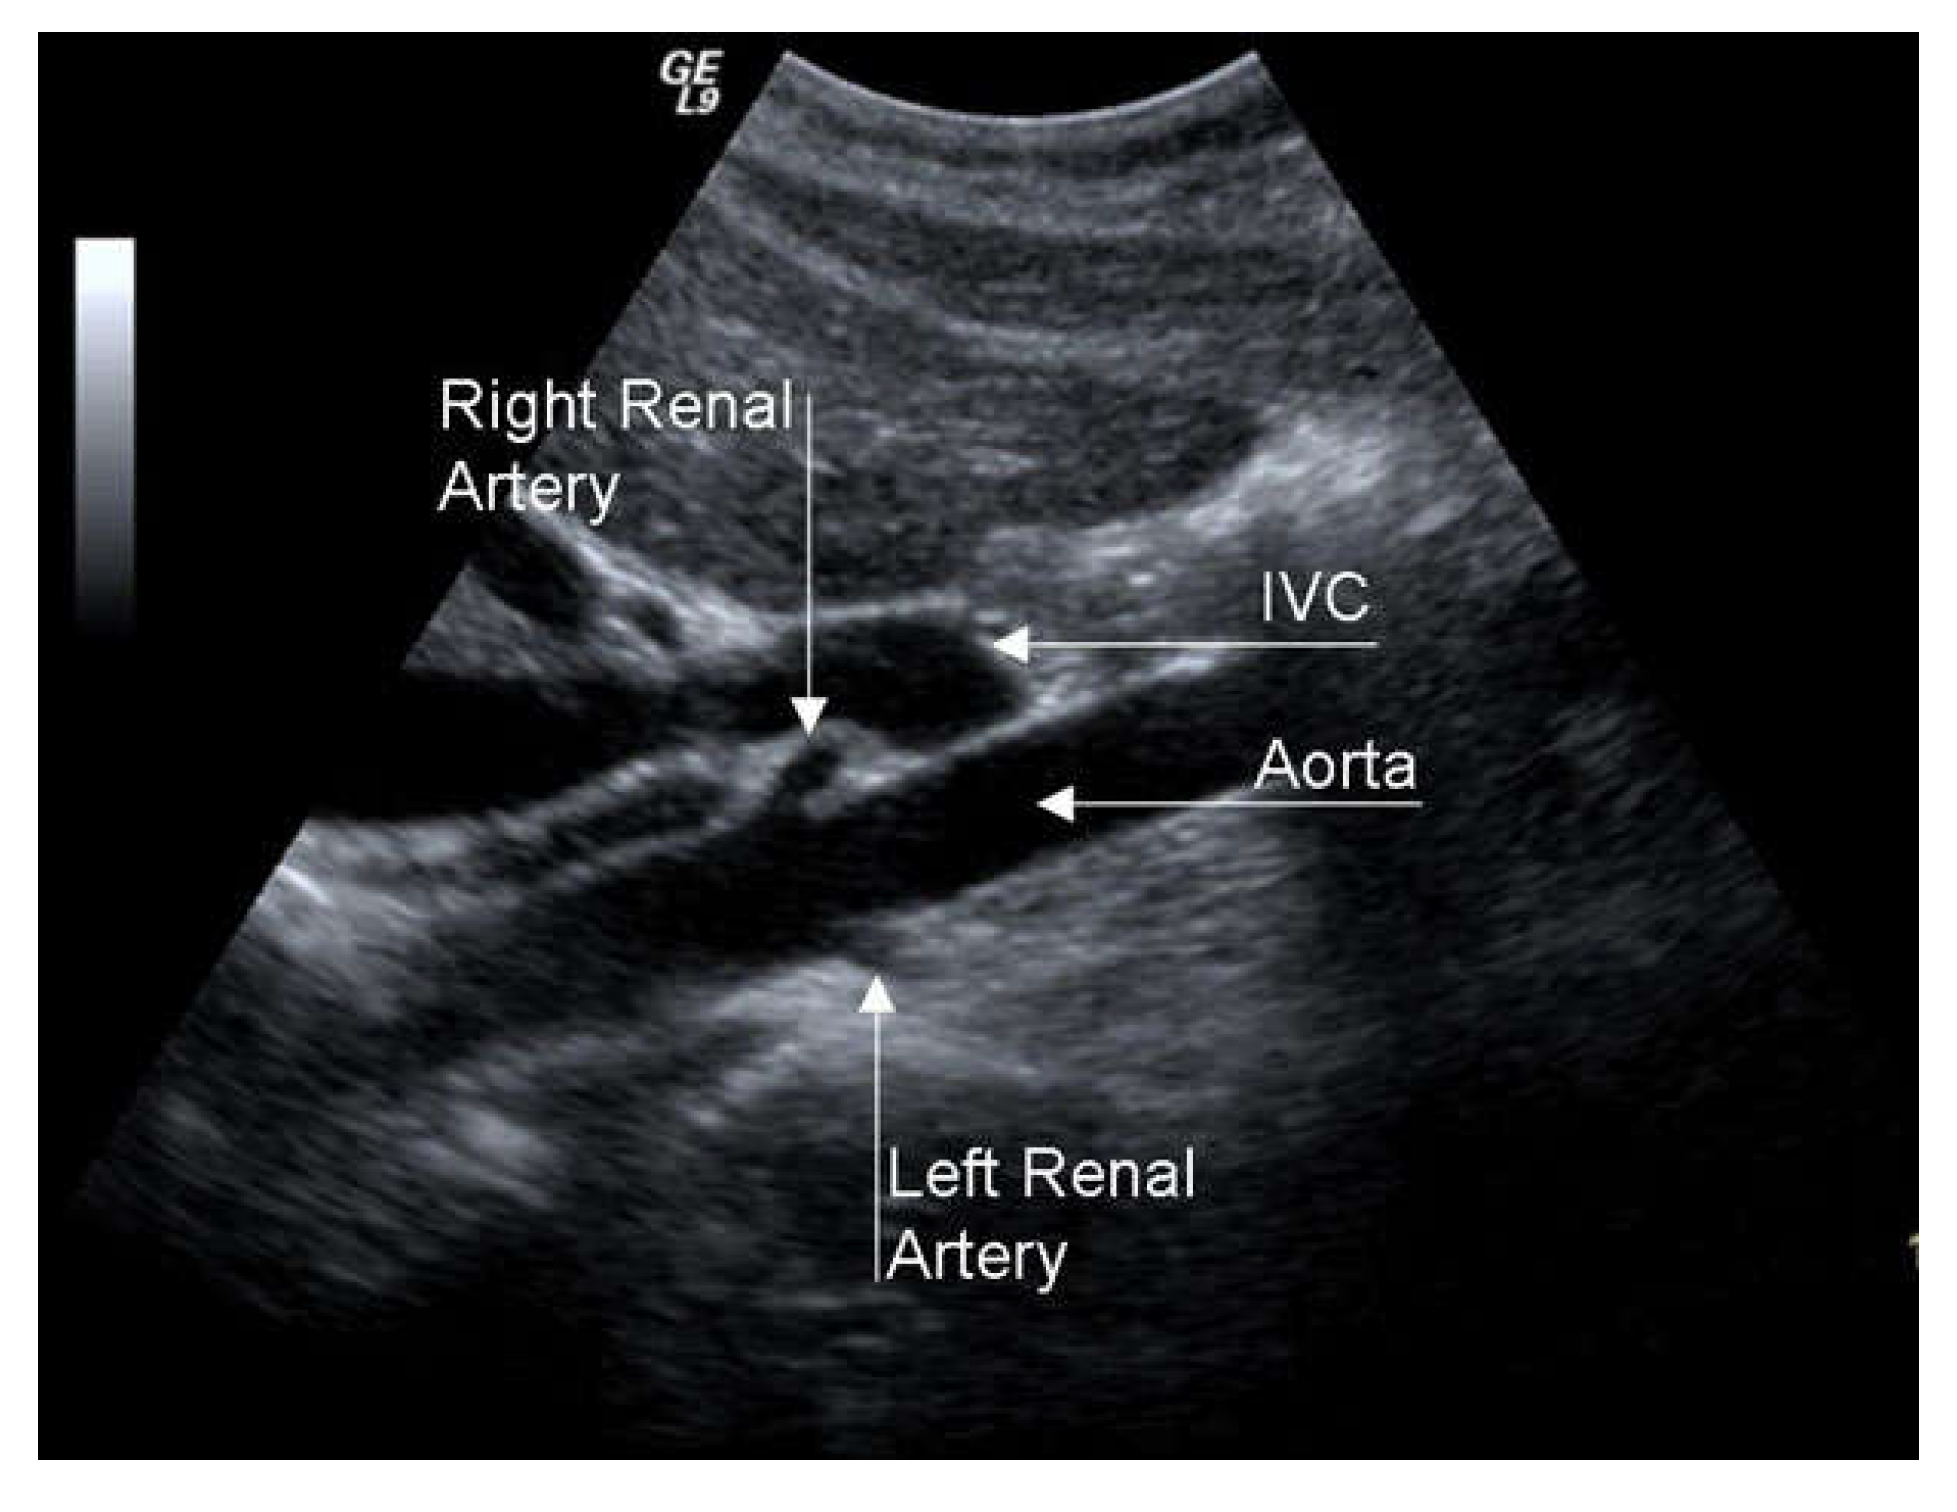

RAS is associated with renovascular hypertension (RVH) and chronic renal insufficiency (CRI), so it configures the clinical picture of renovascular disease (RVD). RAS greater than 50% causes dysregulation of the renin-angiotensin-aldosterone mechanism, which can cause RVH. The differential diagnosis between RVH and essential hypertension is difficult since specific symptoms and signs are lacking. However, RVH should be suspected in some patients since, if not adequately pharmacologically controlled, in the long-term, it brings parenchymal alterations, even in the contralateral kidney, with reduced excretory capacity. The search for RAS passes through a high propensity for clinical suspicion in severely hypertensive patients resistant to medical therapy (RVH is more resistant to pharmacological treatment than essential hypertension) with chronic renal insufficiency, advanced age, coronary artery disease, EICS, or LEAD. A duplex scan is an excellent examination for RAS screening, even if its efficacy is limited in obese patients or with intestinal meteorism (Figure 9).

Figure 9. Duplex scan of the renal arteries (long axis view). IVC, inferior vena cava.